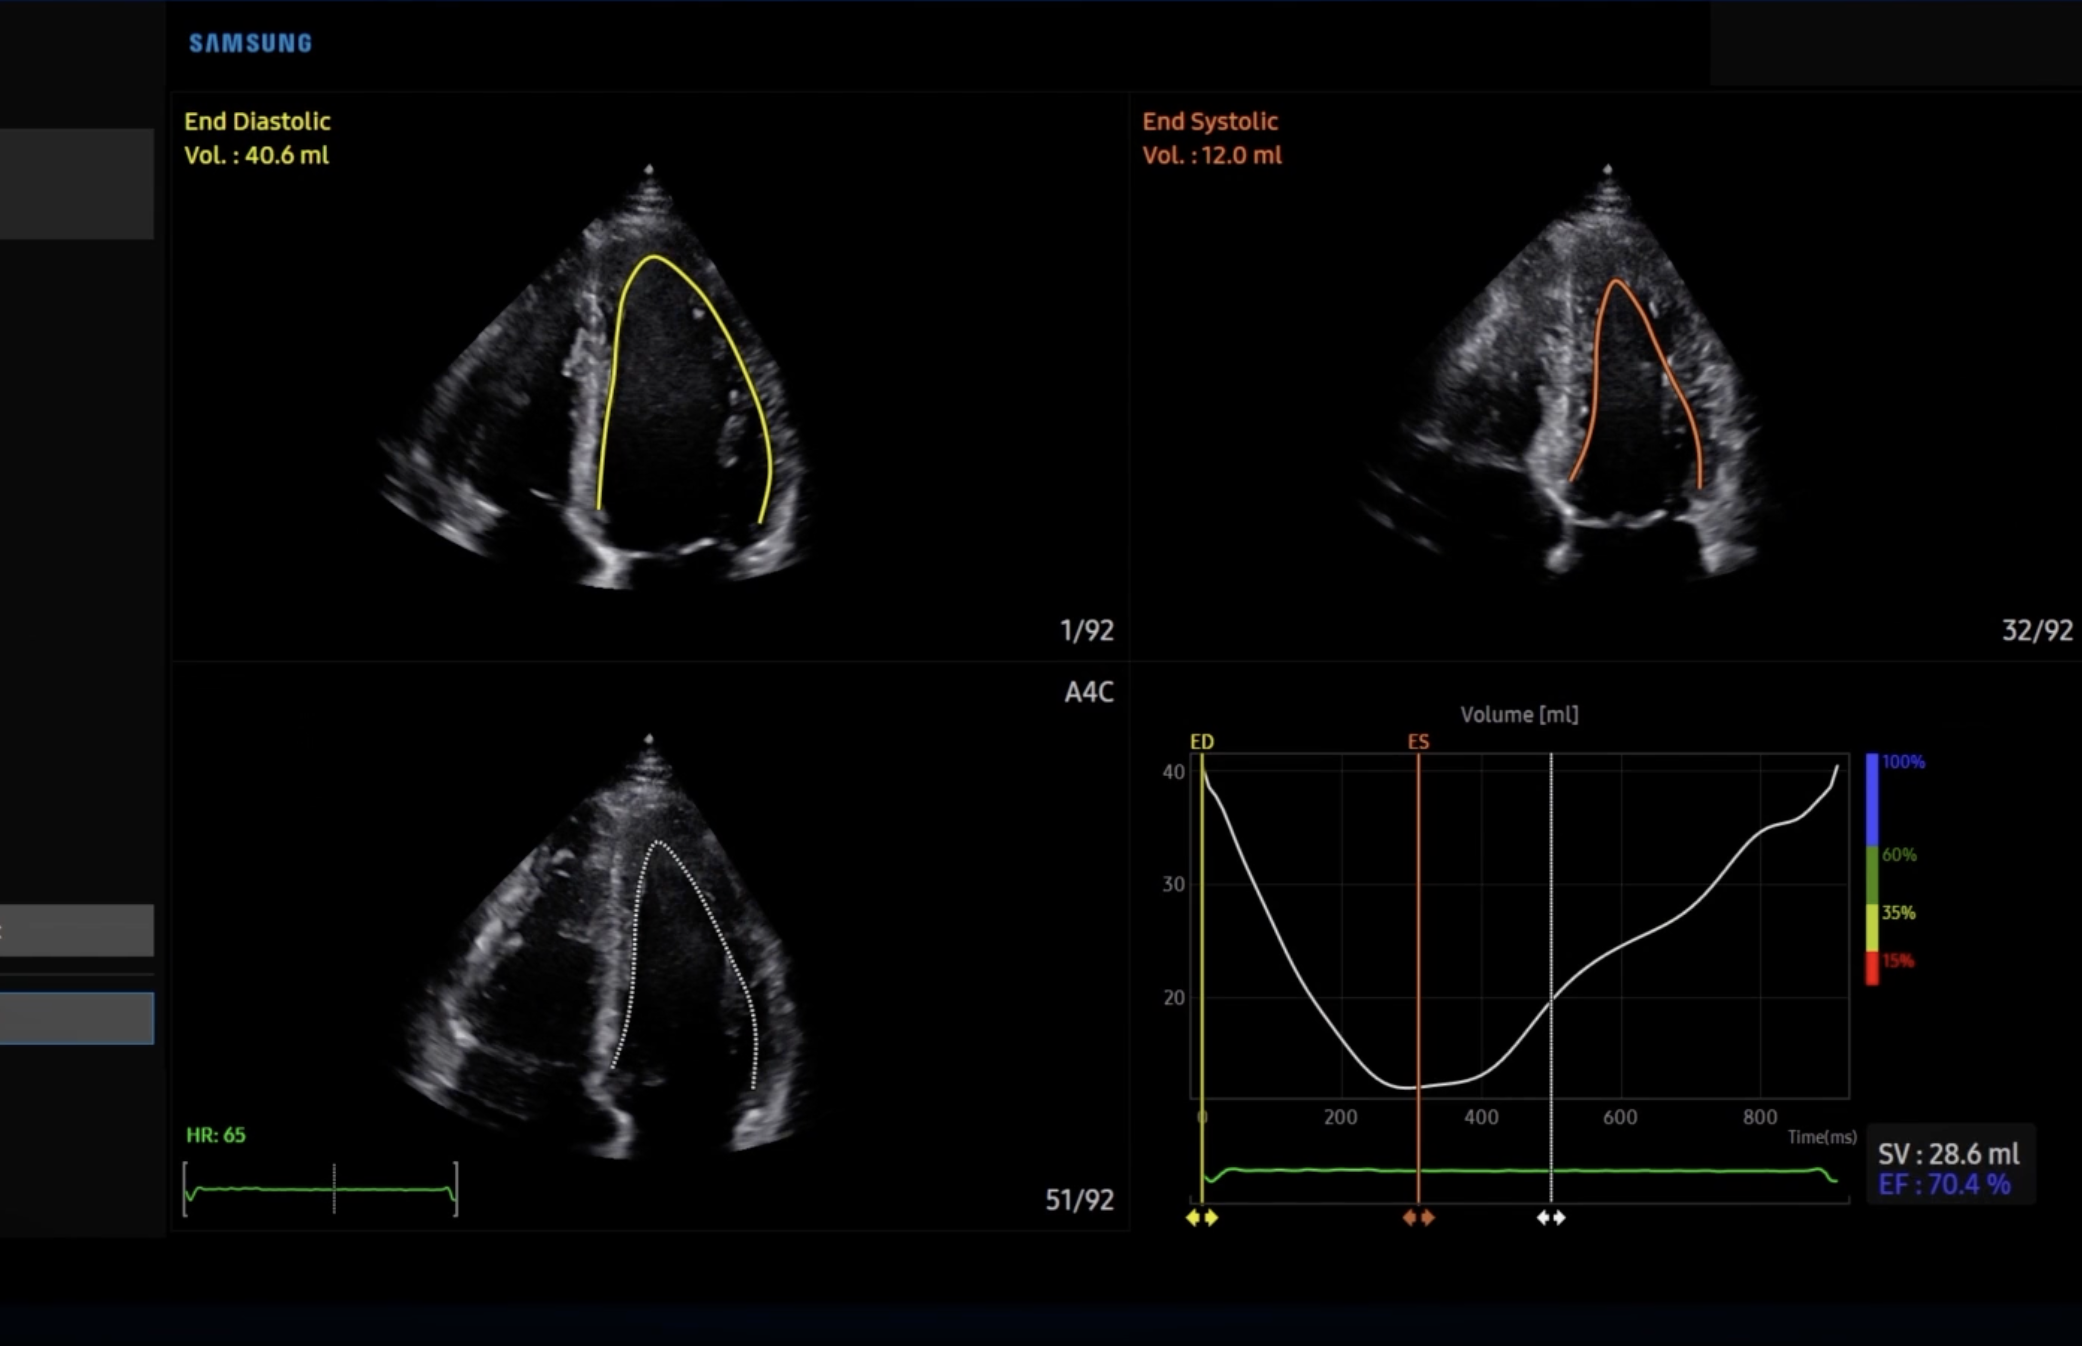

Technische Ausstattung

Entsprechend den Anforderungen unseres breiten Schwerpunktes verfügen wir über alle diagnostischen Möglichkeiten der konservativen Medizin und Diagnostik

Technik

Es ist unsere Grundüberzeugung, daß Technik dem Menschen folgt und und nicht umgekehrt.

Alle technischen Untersuchungen sind Bestätigungsuntersuchungen im Gespräch und der körperlichen Untersuchung erhobener Befunde.

Diese Grundphilsophie stellt sehr hohe Anforderungen an die Hardware. Wir verwenden nur Hardware der renomiertesten Hersteller aus der Schweiz, den USA und Japan.